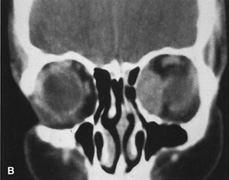

HISTORY AND PHYSICAL EXAMINATION A wide range of signs and symptoms may alert the ophthalmologist to involvement of the orbit by a pathologic process. These include proptosis or globe displacement; compressive optic neuropathy with visual field or visual acuity loss; refractive changes such as progressive hyperopia, restricted eye movements, and diplopia; optic disc changes, including pallor or edema; and fundus changes such as choroidal folds. These manifestations may be the consequences of a primary intraorbital disease or may occur secondary to involvement of the orbit by a process extending from the overlying soft tissues, periorbital sinuses, or intracranial cavity. All patients with suspected orbital pathology should have a thorough ophthalmic history and physical examination. Detailed questioning about the nature, onset, and progression of the chief complaint is necessary to formulate a differential diagnosis. Previous ocular and general medical history related to diseases, operations, medications, and family history should be obtained. A general review of systems will identify risk factors for related systemic diseases, such as hyperthyroidism, metastatic cancer, or lymphoma. A complete examination of the eye and periocular tissues is essential. Abnormal protrusion or displacement of the globe, extraocular motility disturbances, soft-tissue changes, and decreased corneal or periorbital cutaneous sensation should be specifically sought. Special attention always should be directed to evaluation of optic nerve function. Visual acuity testing alone is not sufficient because visual acuity often is preserved initially in patients with compressive optic neuropathy. All patients should be examined closely for detection of an afferent pupillary defect, abnormal color vision, or loss of contrast sensitivity. Formal perimetry should be performed to rule out peripheral field loss. If the presentation has been gradual, evaluation of old photographs may help establish the time course of the pathologic process. In selected cases, appropriate blood work to help identify orbital inflammatory or neoplastic processes also should be obtained. ORBITAL IMAGING Valuable information about the nature and extent of an orbital pathologic process is provided by imaging studies such as computed tomography (CT) scan, magnetic resonance imaging (MRI), and orbital echography. Better spatial resolution, ready accessibility, and lower cost make CT the preferred choice for orbital imaging in most cases. Orbital fat provides a natural contrast between most adjacent orbital structures on CT scanning, and orbital bones are visualized well. Computed tomography is essential for evaluation of the orbital bones because they cannot be imaged with MRI. Direct coronal or sagittal images are important to identify the relationship of a lesion to the optic nerve so that the surgical approach can be planned to avoid traversing the optic nerve (Fig. 1). Newer multislice helical CT scanners allow continuous acquisition of data so that a single rapid pass allows formatting in axial, coronal, and sagittal planes. Multislice CT provides shorter examination times with reduced motion artifact and radiation exposure when compared with conventional CT. Magnetic resonance imaging is useful in selected cases, especially when evaluating the orbital cranial junction. Significant bony artifact and a lack of orbital fat in the orbital apex make CT scan resolution of the orbital apex structures poor. Because cortical bone has low signal on MRI, there is no bone artifact when viewing the orbital apex on MRI. The lack of intervening fat in the apex to provide contrast is overcome on MRI because contrast is provided by the individual nuclear characteristics of each tissue so that the orbital apex structures are visualized well. Consequently, conditions that affect the optic nerve and chiasm, such as optic nerve meningioma and glioma, generally are evaluated with MRI rather than CT scan (Fig. 2). Use of a contrast agent such as gadolinium can further enhance the T1 signal intensity of lesions and is particularly helpful in imaging areas where there has been a breakdown in the blood–brain barrier. Because orbital fat produces a bright signal on T1-weighted images, orbital MR usually is performed with “fat suppression” to prevent masking of lesions. However, incomplete fat suppression can produce artifacts that may be misinterpreted as abnormal enhancement. A few other orbital conditions are better visualized with MRI than CT scanning.1–3 Often, organic foreign bodies, such as wood, are not imaged well with CT scan. These foreign bodies often are visible with MRI. However, care must be taken when imaging any metallic intraocular or intraorbital foreign body because the strong magnetic field of the MR scanner may cause the foreign body to shift position and damage surrounding structures. In some tumors and vascular anomalies, high blood flow is appreciated on MRI. This is caused by a lack of signal, known as a flow void, created by blood flowing rapidly through larger vessels. Tumors that originate in the brain and extend into the orbit secondarily, such as sphenoid wing meningioma, also are visualized well with MRI. However, bony detail and calcification within the meningioma are not imaged well. In unusual circumstances such as this, CT scan and MRI may prove to be complementary, and both techniques may be required to fully evaluate the orbital disease process. Orbital echography can provide useful information in the evaluation of orbital disorders. Because each tissue has its own acoustic characteristics, echography can provide a high degree of tissue contrast. Spatial resolution also is quite good. In some situations, echography can provide information not available on CT scan or MRI. These instances include detection and measurement of blood flow4 and intraoperative localization of small foreign bodies.5 Orbital echography requires specialized equipment and a large amount of expertise to obtain the detailed information that is readily available with CT scan or MRI; consequently, its use has decreased. Recent advances in orbital imaging have been summarized by Lee and colleagues.6 |